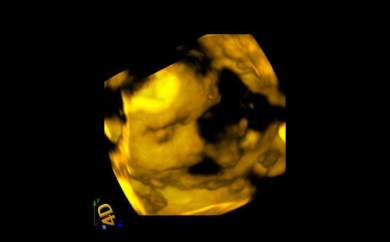

Es la última que nos envía sus ecografías. Solo tiene 18 años. Ha conseguido poder pagarse unas ecografías en 4D. Nos las ha enviado a toda la asociación. Se llama Merce

des y es una de las menores de 20 años que tenemos en los cursos de la asociación. Está tan feliz que se ha puesto a estudiar.

Viene a todo lo que la convocamos. Y ella también nos hace felices a nosotros. La hemos prometido que le pondríamos sus ecografias en este blog para que lo puedan ver todos los rescatadores Juan Pablo II. Como nos comentó hace dos días, parece mentira que hace 5 meses intentara abortar a su hijo. Hoy empieza su tercer trimestre de embarazo. Asociación MásFuturo